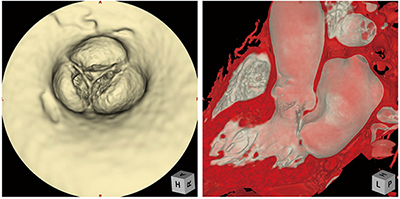

■ Ziostation2を用いた臨床画像

大動脈離断症の3D再構成画像心臓、大動脈、肺動静脈を色分けして術前のシミュレーション情報を提供。

同症例の手術に人工血管ではなく患者自身の血管を使ったのは世界初。

大動脈弁閉鎖不全症のPhyZiodynamicsによる処理画像